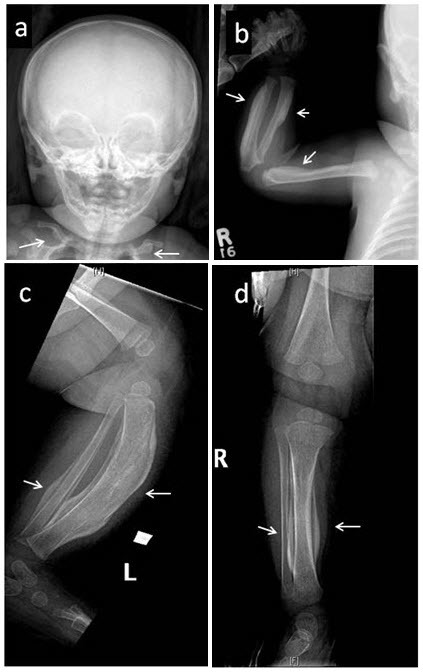

Figure 1. . Skeletal survey in a female age five weeks with the defining COL1A1 p.

圖1:對一名五周齡女性進(jìn)行的骨骼調(diào)查,該女性具有明確的 COL1A1 p.Arg1014Cys 致病性變異,其右脛骨出現(xiàn)疼痛性腫脹。注意廣泛參與 (a) 涉及下頜骨和鎖骨的對稱雙側(cè)骨膜反應(yīng); (b) 肱骨、橈骨近端軸和尺骨遠(yuǎn)端軸的不對稱受累; 和 (c,d) 脛骨和腓骨。箭頭指向顯著的骨膜下增厚和彎曲。 還注意到髂骨、股骨、脛骨和左腓骨的不對稱反應(yīng)(未顯示)。 癥狀在發(fā)作后一個月內(nèi)消失。